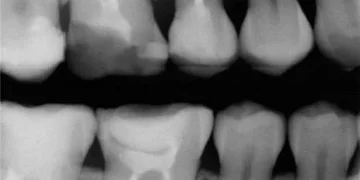

Рентген зуба при беременности является темой, требующей особого внимания и осторожности. Во время беременности женщины испытывают множество изменений в организме, и здоровье зубов не исключение. Основное беспокойство связано с воздействием рентгеновских лучей на развивающийся плод. Однако современные методы рентгенографии, включая защитные меры, минимизируют риск, и многие врачи считают, что в некоторых случаях проведение рентгенографии необходимо для обеспечения адекватного лечения зубов.

Важно отметить, что рентгеновский снимок зуба может быть рекомендован в экстренных случаях, когда существует риск серьезных осложнений. Например, если у женщины развивается зубной абсцесс или другие неотложные стоматологические проблемы, рентгенография может стать единственным способом выявить проблему и выбрать правильную тактику лечения. В таких случаях приоритетом является здоровье матери и будущего ребенка, и следует помнить, что не все рентгеновские исследования одинаково опасны.

• Для анализа скрытого кариеса.

• Обследование зуба мудрости: его рост и расположение;

• Выявление и подсчет кист, а также их рост;

• Диагностика перелома корня зуба.